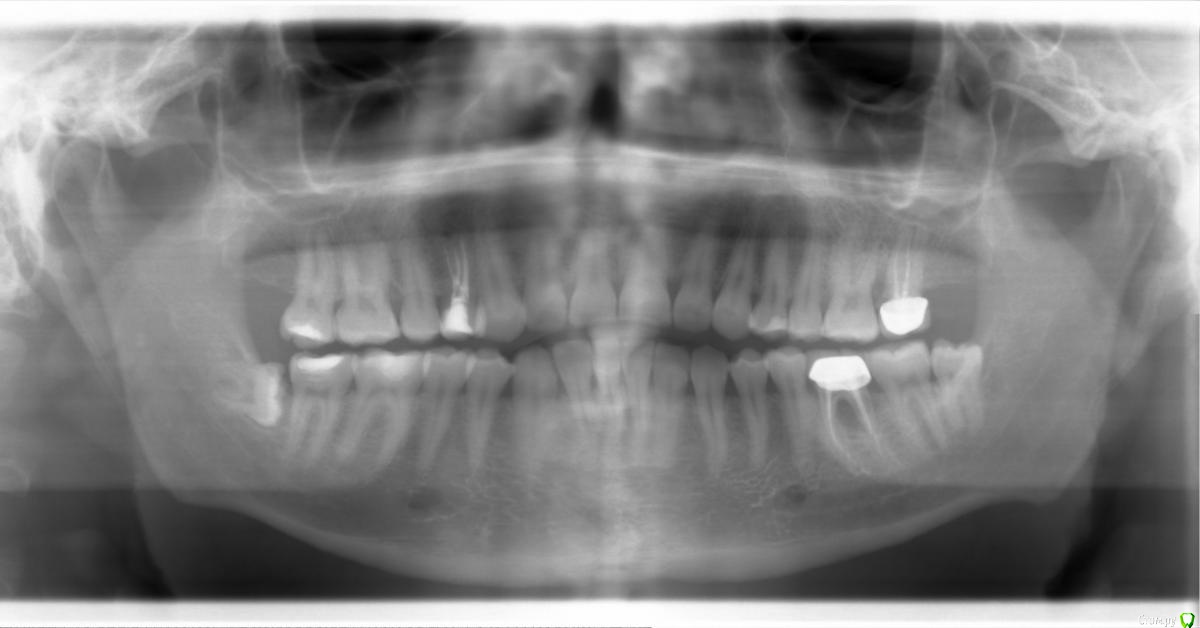

rdr Опубликовано 4 сентября, 2017 Поделиться Опубликовано 4 сентября, 2017 Добрый день! История такая... Сделали коронку на нижний 6 зуб, через некоторое непродолжительное время появился дискомфорт и даже боль в этом зубе. Пришёл к тому же врачу, если правильно помню, то даже сделали рентген, но в итоге врач сказал, что ничего страшного там нет - просто попадает еда в некую пазуху. Сделал промывание и прописал мазать мазью. В итоге боль действительно ушла, я также стал дома промывать зубы ирригатором, но всё же какой-то дискомфорт чувствовался, но я не предавал этому особого значения (видимо, зря). Так продолжалось несколько месяцев, пока на внутренней стенке десны не появился "прыщик". Если правильно понимаю, то правильно он называется свищ. В итоге в одной клинике мне сделали снимок и сказали, что это киста, что её можно попробовать почистить, но есть вероятность, что она вернётся.В ЦНИИС и ЧЛХ сказали примерно то же самое и сделали мне резекцию. Врач сказал наблюдать за зубом. Во-первых, свищ снова появился уже через две недели.. Не слишком ли это быстро после резекции?Во-вторых, собственно, основной вопрос: имеет ли смысл ещё пробовать как-то лечить этот случай, или смириться, удалить зуб и ставить имплант? Снимок прикрепляю. Заранее спасибо за советы! Ссылка на комментарий

red_butler Опубликовано 4 сентября, 2017 Поделиться Опубликовано 4 сентября, 2017 к сожалению качество снимка не позволяет дать однозначный ответ. Ссылка на комментарий

St. Опубликовано 4 сентября, 2017 Поделиться Опубликовано 4 сентября, 2017 (изменено) Снимок действительно не очень хороший. Но по нему необходимости в резекции как таковой я не увидела, поскольку зона "воспаления" находится не на верхушке какого-то из корней, а между ними. Соответственно результата от такой манипуляции не получилось.Вариантов собственно 3 - или перелечивать каналы и чистить корень вокруг, или не трогать или удалять.Лично я за удаление. Перелечивание зубов с такой локализацией воспаления да ещё после резекции дело очень сомнительное.и даже по финансам перелечивание и новая коронка сравнимо с ценой имплантиции, но с большими шансами на успех.А если оставить как есть процесс будет продолжаться и разрушать кость, соответственно когда через время Вы все равно придёте к удалению и имплантации, то условия для ее проведения будут уже гораздо сложнее. Изменено 4 сентября, 2017 пользователем St. Ссылка на комментарий

red_butler Опубликовано 5 сентября, 2017 Поделиться Опубликовано 5 сентября, 2017 А её можно как-то.. что ли.. плохо сделать? Или, даже если делать всё правильно, то всё равно есть шанс не всё удалить?Я понимаю, что 100%й результат не гарантирован, просто очень удивился, что уже через 2 недели всё вернулось. Спасибо за ответы! Только по одному снимку, да еще и плохого качества на эти вопросы не ответить. Нужно знать что было, что делали, что стало. 1 Ссылка на комментарий